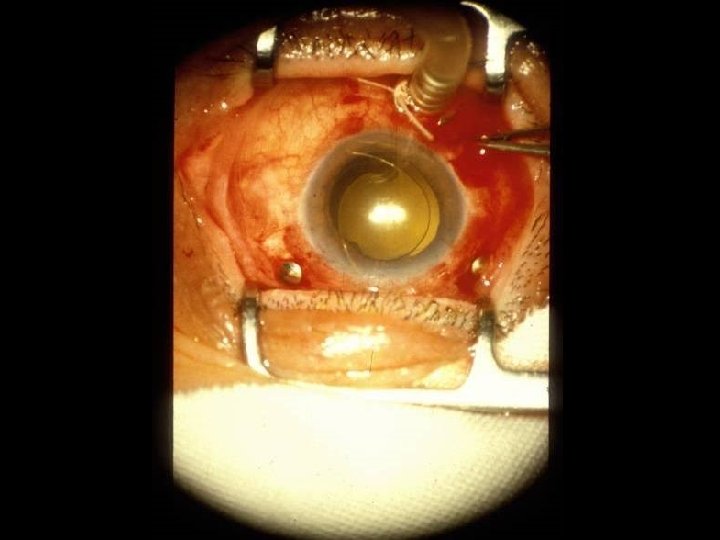

CHIRURGIA AB ESTERNO Tempi operatori Peritotomia congiuntivale Peritotomiacongiuntivale Isolamento dei muscoli retti Apposizione dicerchiaggio in bandelletta di silicone cerchiaggioin bandellettadi larga 2. 5 mm e spessa 0. 5 mm e/opiombaggi in piombaggiin silicone rigido o spugna in silicone Fissazione delcerchiaggio mediante due punti in cerchiaggiomediante mersilene 5/0 per quadrante mersilene 5/0 Annodamento delcerchiaggio con piccolo anello di cerchiaggiocon silicone Drenaggio del liquido sottoretinico Sutura della congiuntiva invicryl 8/0 Pessia ? ( crio ? laser ? )

CHIRURGIA AB INTERNO Tempi operatori Apertura della congiuntiva e della sclera a 3. 5 -4 mm dal limbus Vitrectomia centrale e periferica Segmentazione delle membrane epiretiniche e talvolta sottoretiniche Immisione di sostanze reintegranti o tamponanti quali: Bss , aria, miscele di gas espansibili (sf 6, c 3 f 8, etc. . ) olio di silicone, doppio tampone Endodiatermia, fotocoagulazioine Sutura della sclera in vicryl 7/0 , della congiuntiva in vicryl 8/0